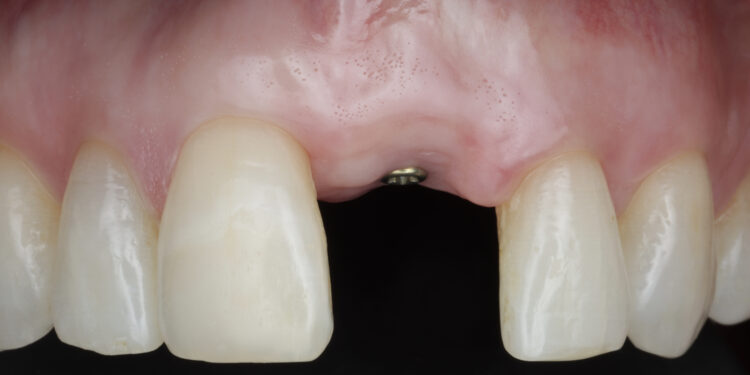

Once the orthodontic treatment was completed, the site was re-evaluated, and it was clear to see that the gingival zenith had significantly improved. The patient was advised that without re-contouring the mesial aspect of the contralateral central incisor there would be a midline black triangle. She rejected the option of composite addition to alter the triangular shape of the UR1 and thus we proceeded to complete the treatment without this. The implant was placed with simultaneous buccal GBR & connective tissue graft following a transmucosal approach. Following a healing period of 4 months, the restorative treatment was initiated with a temporary crown to develop the emergence profile. Once the gingival zeniths had been matched, the patient was delivered a permanent screw retained crown.